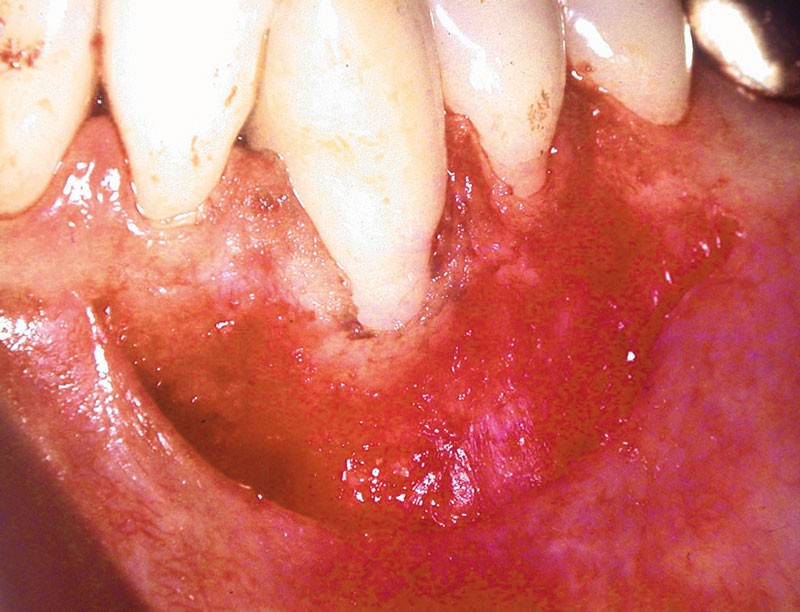

Dans ce deuxième cas, la canine mandibulaire présente également une absence de gencive attachée, associée ici à une récession gingivale (fig. 3).

Une greffe épithélio-conjonctive est réalisée (fig. 4).

Positionnée plus coronairement que la précédente (fig. 5), elle permettra de recouvrir la récession et de recréer un lambeau de gencive attachée (fig. 6).